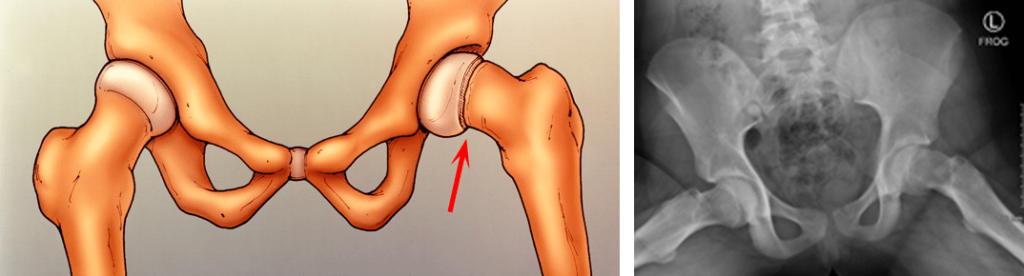

Illustration and X-ray of in situ fixation. A single screw is inserted to prevent any further slip of the femoral head through the growth plate.